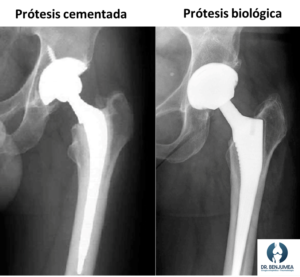

Tipos de prótesis de cadera

Hay dos grandes grupos, en función de cómo se fijan al hueso.

Prótesis cementadas: Son aquellas que deben emplear un cemento que las ancle al hueso. Solemos recomendarlas en personas mayores con un hueso debilitado. Es habitual emplearlas en los casos de fractura de cadera.

Prótesis biológicas (press-fit): Son prótesis que en un primer momento se agarran mediante presión, y que presentan un material provoca que el hueso del paciente pueda “crecer” hacia adentro de la prótesis, integrándola en el propio cuerpo. Se recomiendan en pacientes con un hueso que aun sea fuerte. Es la más empleada en el caso de artrosis de cadera.